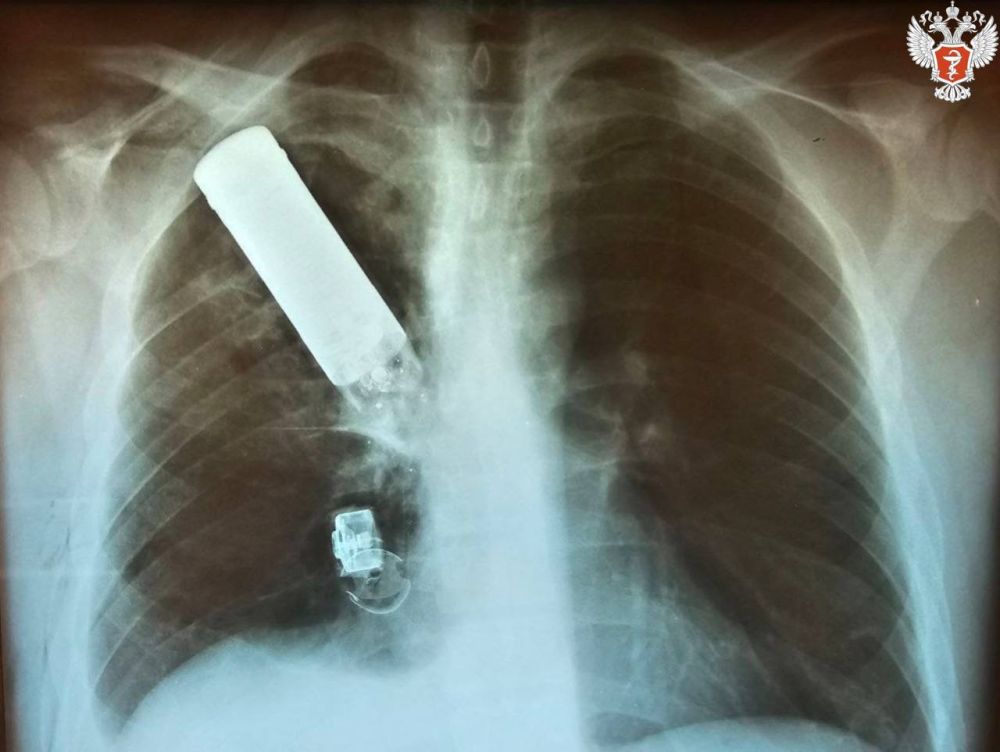

В одну из больниц Донецка поступил боец, в груди которого застрял осколок гранаты. Кусок боеприпаса мог взорваться в любой момент, но врачи, рискуя собой, смогли аккуратно вытащить его. Об...